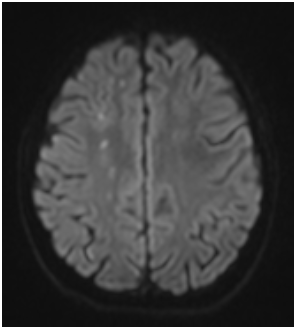

A 14-year-old female presented with subacute onset of random, unintentional movements involving the neck, trunk, limbs as well as facial muscles. The movements were sever enough to interfere with mobility. Otherwise she did not have any systemic complaints. Had no history of a recent infectious illness and did not use any medication. Her past and family history was unremarkable. On examination, she was alert, fully oriented with intact cognitive functions. The movements were noted as involuntary, rapid and purposeless generalized movements. She could not control it and had difficulty stabilizing her head. Auscultation revealed pansystolic murmur over the apex. She had no skin lesion, joint tenderness or swelling. Blood investigations showed normochromic normocytic anemia with thrombocytopenia (Hb: 8g/dl, MCV: 80 fl, WBCs: 4.5×10⁹ Platelets: 84×10⁹). Had normal renal and liver functions. Coombs test was positive, ANA and anti-dsDNA Abs were positive. Furthermore her cardiolipin IgG was positive (36.9 U/ml) and urine analysis shows hematuria (20-30/HPF) and proteinuria (100 mg/dl). Brain MRI demonstrated multiple bilateral old and recent ischemic lesions (Figure 1). Echocardiography show mildly thickened mitral valve with prolapsed of anterior segments of mitral leaflet & moderate mitral regurgitation.

Figure 1 (A & C) FLAIR and (B & D) Diffusion-weighted images of the brain showing multiple small infarctions at different ages (old and recent) involving the deep white matter of both cerebral hemispheres. The acute infarcts show diffusion restriction on B & D, while old infarctions show low signal on FLAIR images with surrounding gliosis.